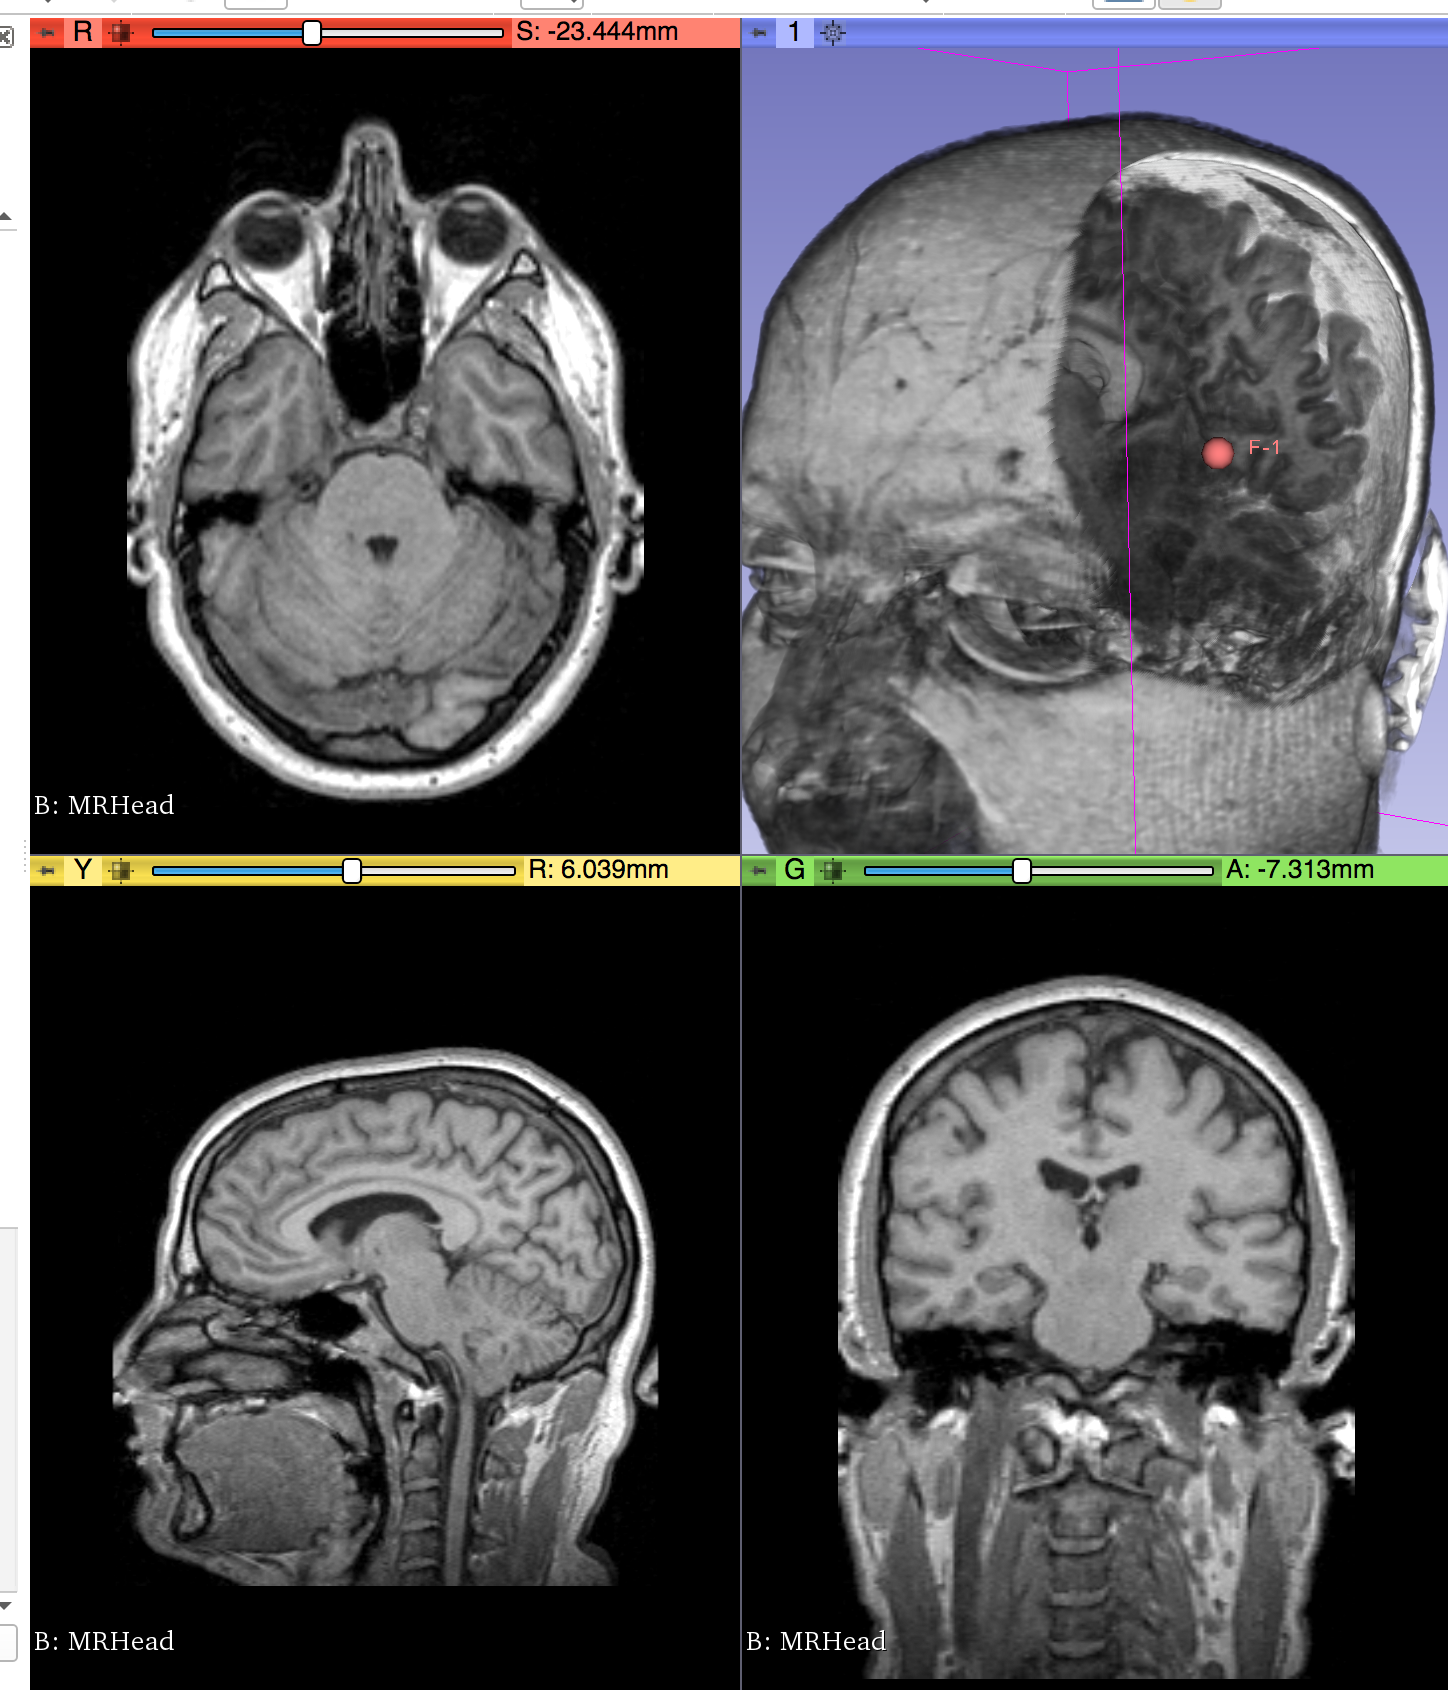

| Philips 3D US | Chroma-depth in PRISM | Depth peeling in PRISM |

|---|---|---|

![]() |

| Edge enhancement in PRISM | Decluttering in PRISM | Volume carving in PRISM |

| Blood flow animation in PRISM | ||